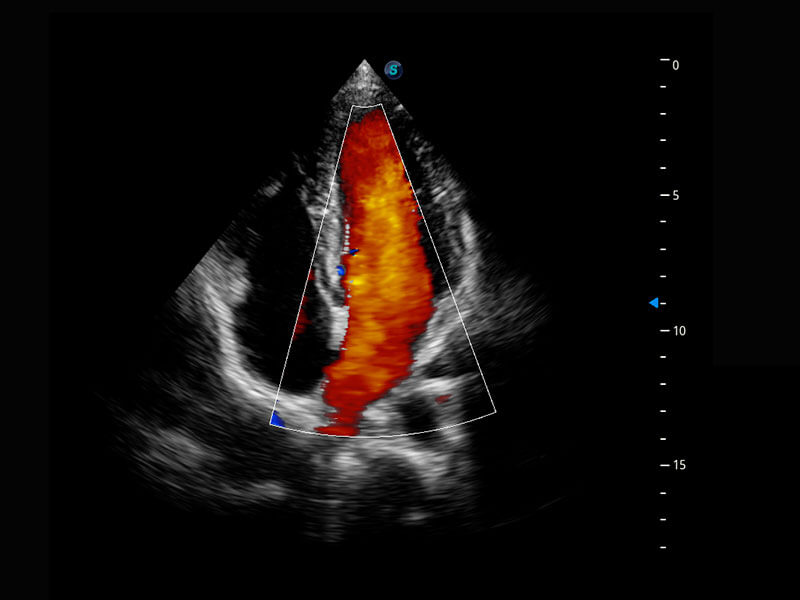

P60搭載一系列胎兒心臟成像技術(shù),實(shí)現(xiàn)精細(xì)的胎兒心臟評(píng)估。

四腔切面

四腔心血流